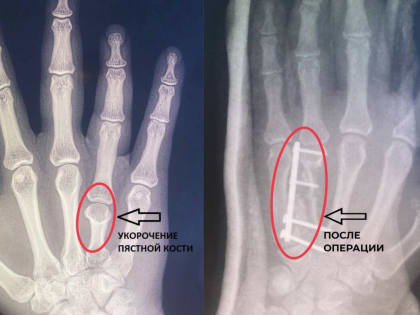

Во Владимире врачи удлинили девушке безымянный палец

Владимирские врачи из областного центра спецмедпомощи сделали жизнь одной девушки проще, удлиннив ей безымянный палец на правой руке.